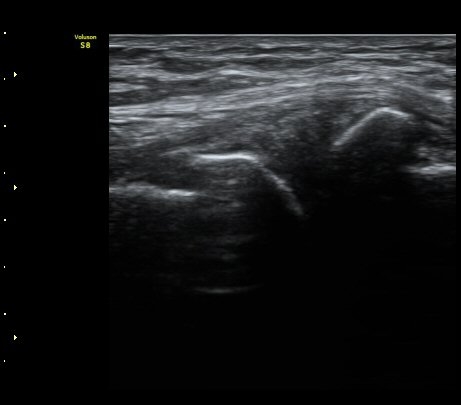

¹«¸­ ³»Ãø Á¾´Ü¸é°Ë»ç»ó ½ÉÇÑ °ñ±Ø°ú ¹Ý¿ù»ó¿¬°ñ Ç¥ÃþÀ¸·Î µ¹ÃâÀÌ °üÂûµÊ(»çÁø 1)